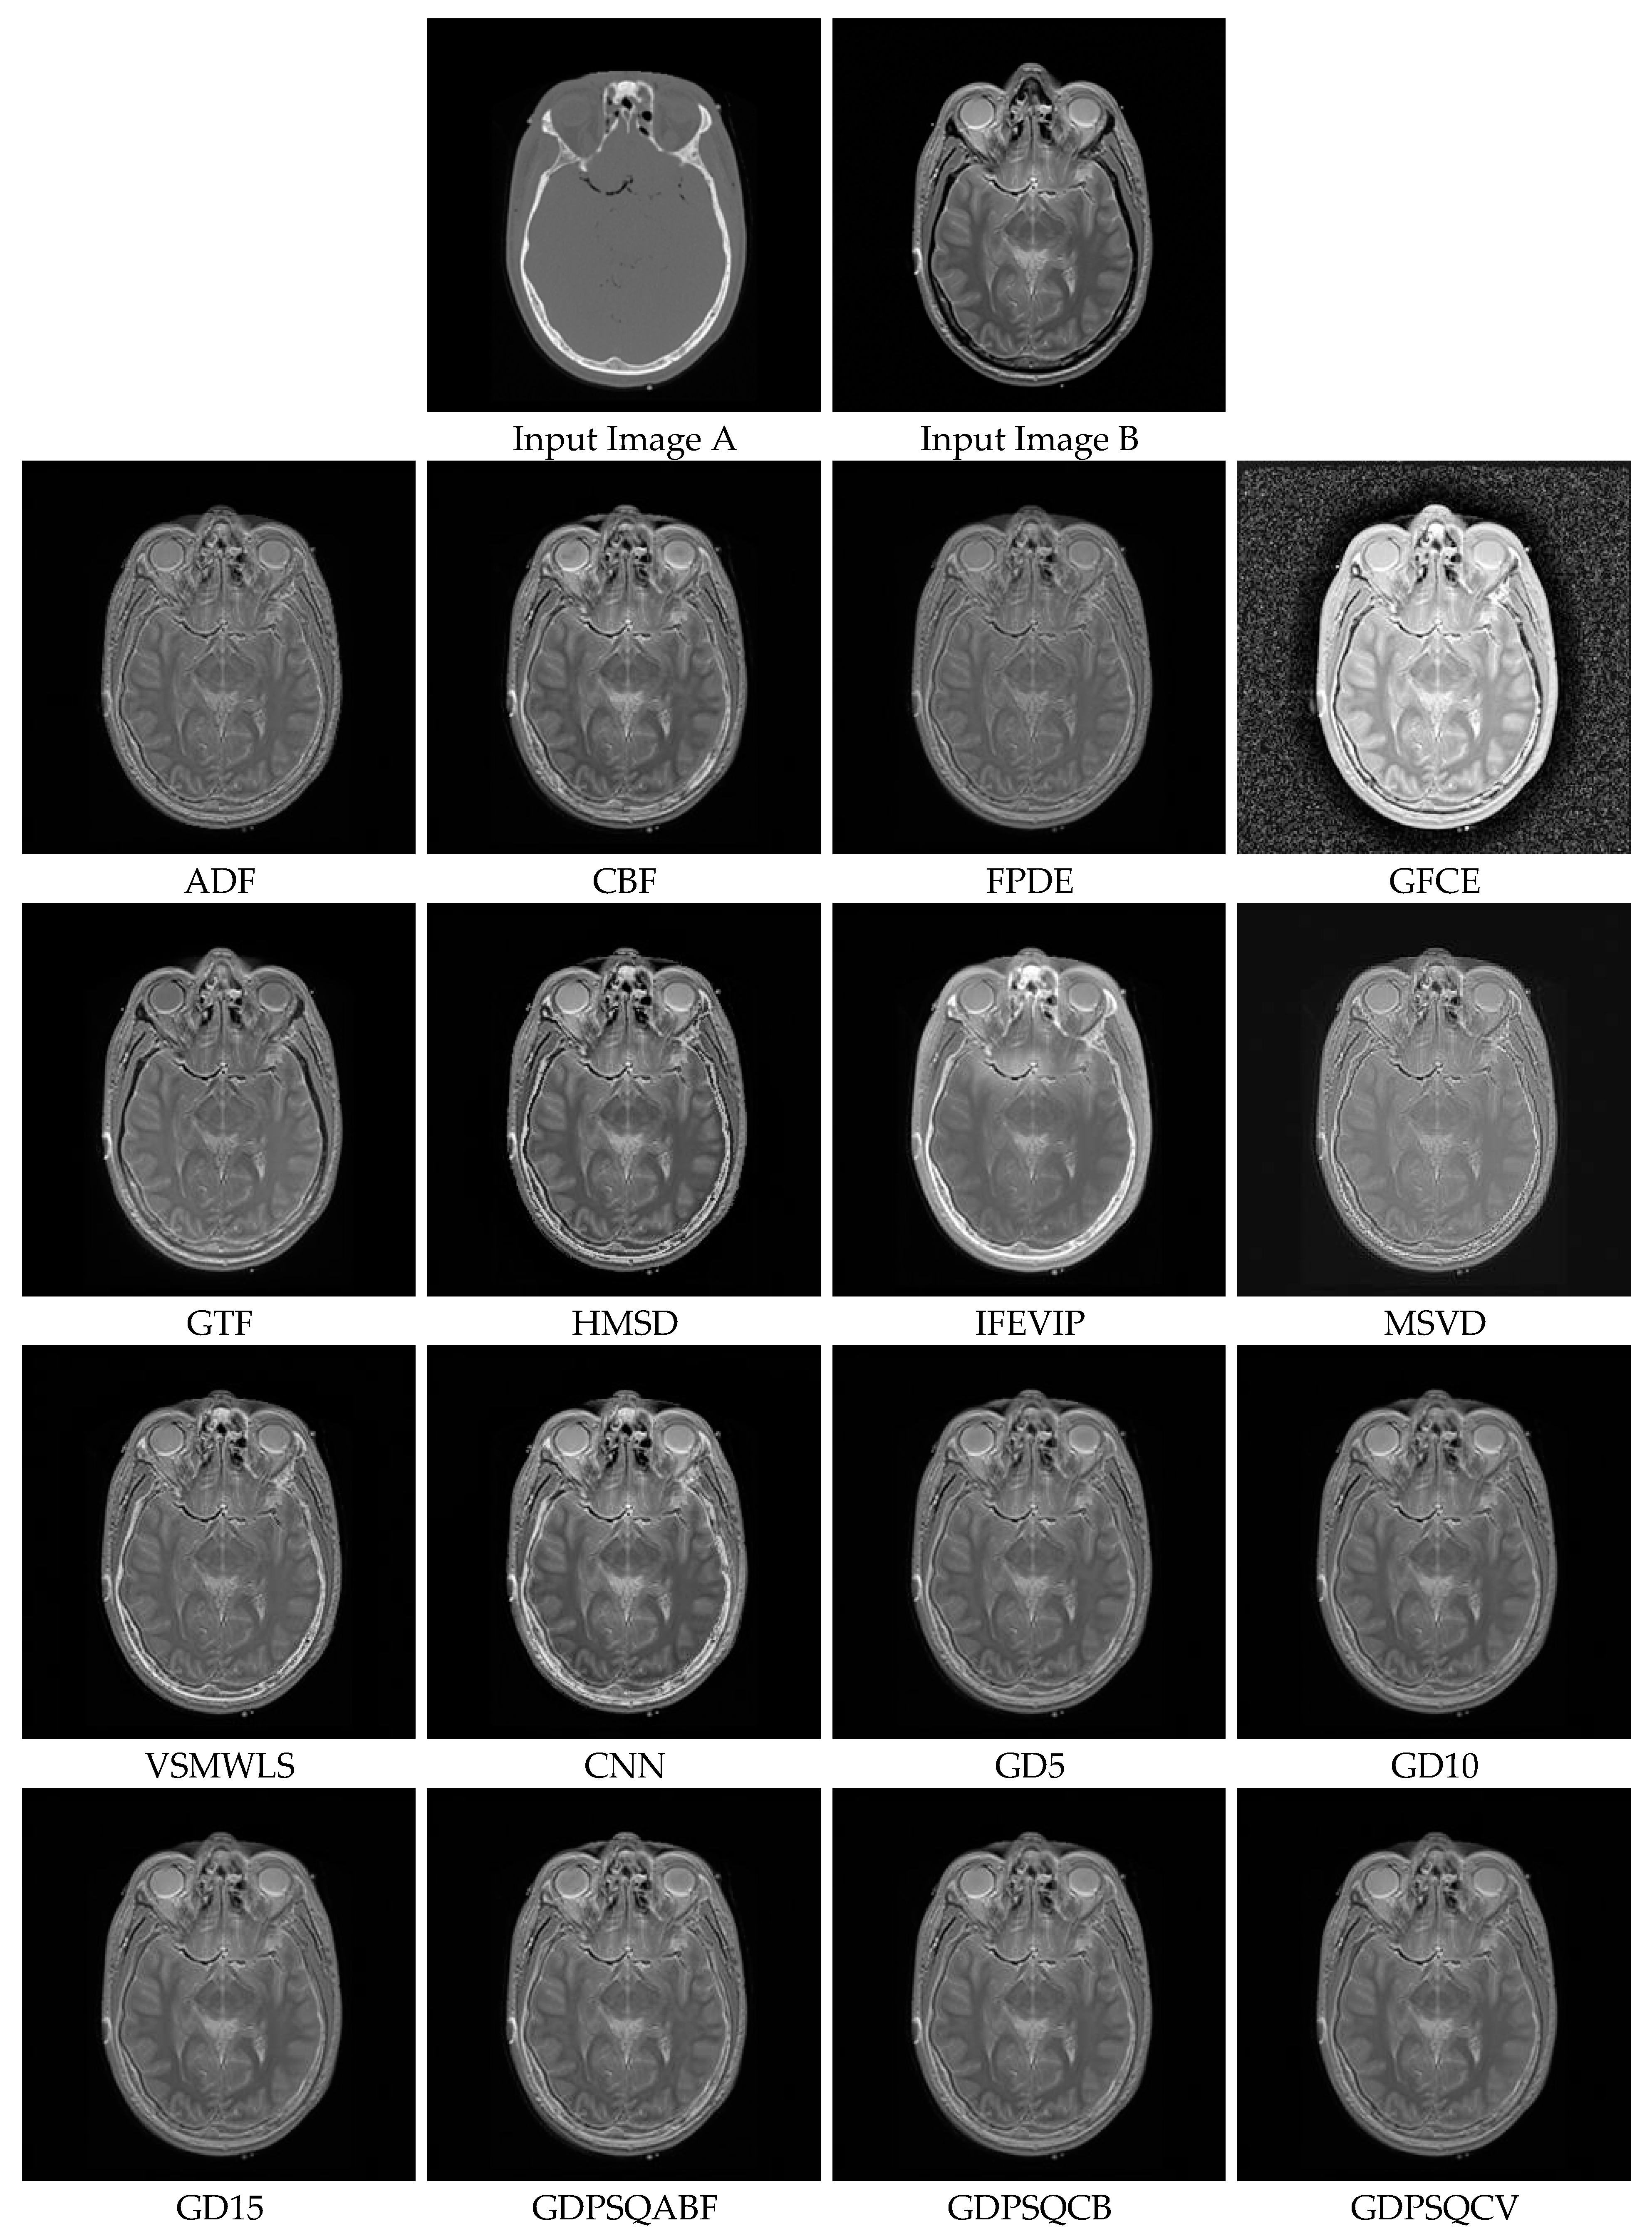

For this sub-section, medical images M#2 and M#5, shown in Figure 9, were selected from eight candidates among the dataset and tested. The visual fusion results of image set M#2 are given in Figure 13. Input Image A is a computed tomography (CT) slice image of the human brain, and Image B is a magnetic resonance (MR) image of the same section. In an ideal case, the bright bone features shown in the CT image and the tissue features shown in the MR image should be included in the fused image. As can be seen from the visual results, the GFCE image has obvious noise in the background. The FPDE and MSVD images lack contrast. The IFEVIP and VSMWSL images resemble mostly Input A (CT) and ignore Input B (MR). As a result, the ADF, CBF, GTF, HMSD, and proposed GD methods show better visual performance than others.

In Table 4, the numerical results of the quality metrics of the comparison methods for M#2 are given. As can be seen in the table, the VSMWLS, proposed GD15, and proposed GDPSQCV methods show better performance according to the numerical metrics. On the other hand, GFGC, ADF, and IFEVIP show the worst performance compared to the others.

Figure 13. Medical image set M#2 (Images A and B) and their fusion image results, obtained using comparison methods.

Entropy 25 01215 g013